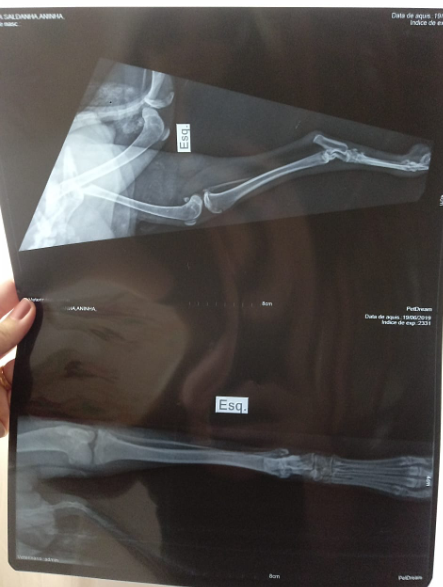

Oi, eu sou a Aninha! Fui atropelada quando estava nas ruas, e passei 3 semanas me arrastando na lama e nas chuvas até ser resgatada. Fui violentada por algum objeto que não sei dizer. Quebrei a coluna e preciso urgentemente me operar, para que possa ter a esperança de dias mais felizes, com ou sem carrinho. Preciso parar se sentir dor. Já sinto amor e segurança, fui resgatada e não volto pras ruas

ATUALIZAÇÃO - 25/06 Hoje faz uma semana que Aninha saiu das ruas, pelo olhar sensível da Tia Monara e do Tio Marcos. Ela não tem mais pulgas e carrapatos, esta vermifugada, come bem. Fez exames e descobriu que quebrou a coluna, precisará de cirurgia para estabilizá-la e reduzir as dores. Usará fraldas, por enquanto não controla o cocô e o xixi. Mas já está fazendo os dois bem, não precisará mais de lavagem, se Deus quiser. Essa semana repetiremos o hemograma, para ver se as taxas melhoraram, e continuaremos tentando organizar a cirurgia. Nada disso é tão importante em saber que, em uma semana, ela se arrasta pela casa toda, adora ficar junto de Luiz, melhora gradualmente a sua relação com Tapi (que continua desconfiada 😂) , vai comer e beber água sozinha, reconhece todo mundo, e vai receber a gente na porta quando chegamos 💝 Ajude Aninha a melhorar a sua qualidade de vida! Se voce puder, contribua na vaquinha virtual. E compartilhe, no insta, no Whatsapp da família, dos amigos. Ela merece ser feliz!